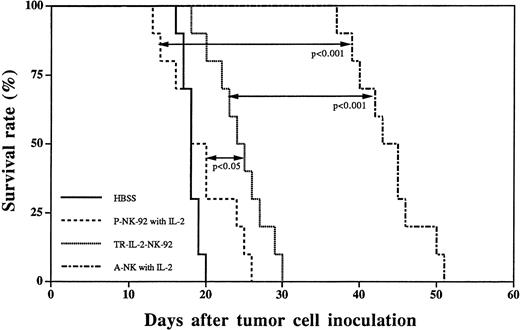

A subset of IL-2–activated human NK cells, A-NK cells, have been previously shown by us to rapidly eliminate established liver metastases of HR, a human gastric carcinoma, and to prolong survival of nude mice treated by adoptive transfer of A-NK cells and IL-2.4 24 In view of our results indicating that TR-IL-2-NK-92 cells have significantly enhanced in vitro antitumor activity against HR targets, we next performed a series of in vivo adoptive immunotherapy experiments in the HR model of liver metastasis, comparing TR-IL-2-NK-92 and P-NK-92 cells. Single adoptive transfer of TR-IL-2-NK-92 cells resulted in significantly prolonged survival of nude mice with 3-day established liver metastases as compared with 3-day therapy with P-NK-92 cells administered together with IP IL-2 (Fig 10). Nevertheless, the therapeutic effect of TR-IL-2-NK-92 cells was not as impressive as with A-NK cells transferred together with exogenous IL-2. P-NK-92 cells plus IL-2 had no therapeutic effect against established liver metastases as compared with tumor-bearing control mice not treated with AIT (Fig10).

Survival curves of nude mice with 3-day established liver metastases following immunotherapy with HBSS control, P-NK-92 cells plus exogenous IL-2, TR-IL-2-NK-92 cells, or A-NK cells plus IL-2. Statistical differences in survival between groups of 10 animals each are indicated.

Survival curves of nude mice with 3-day established liver metastases following immunotherapy with HBSS control, P-NK-92 cells plus exogenous IL-2, TR-IL-2-NK-92 cells, or A-NK cells plus IL-2. Statistical differences in survival between groups of 10 animals each are indicated.